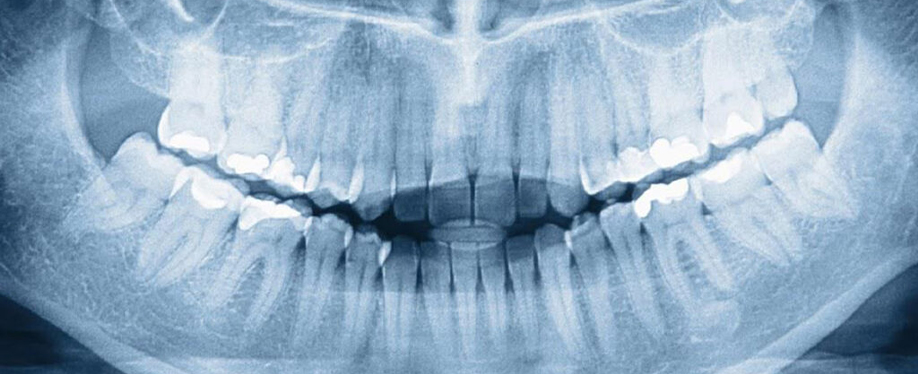

Diş hekimi muayene sorasında diş çürüklerini, dişeti hastalıklarını ve kapanış sorunlarını tespit eder. Yapılacak radyolojik görüntüleme ise arayüz çürükleri, kök ucu enfeksiyonları ve gömülü dişler gibi gözle görülmeyen pek çok sorunu gözler önüne serer.

Oral diagnoz zorunlu mudur?

Oral diagnoz sorunların en doğru şekilde tespit edilebilmesi ve hasta için en uygun tedavi planının çıkartılabilmesi için gereklidir.